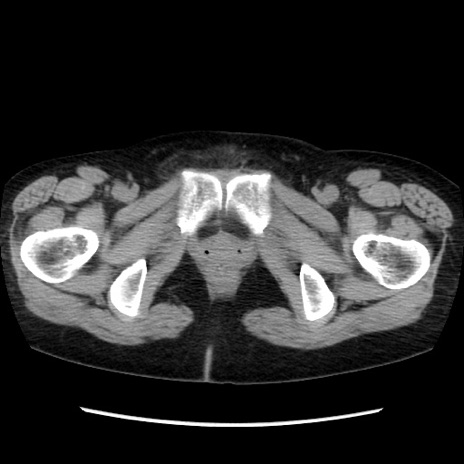

症例32(横断像)

【症例】40歳代 女性

【主訴】上腹部痛、嘔気・嘔吐

【現病歴】約9時間前頃から急に上腹部痛、嘔気、嘔吐が出現。改善しないため救急要請。

【既往歴】子宮頚癌(広汎子宮全摘術、放射線療法)、腸閉塞

【身体所見】腹部:平坦、軟、腸雑音亢進、上腹部を中心に腹部全体に圧痛あり。

【データ】WBC 8400、CRP 0.03